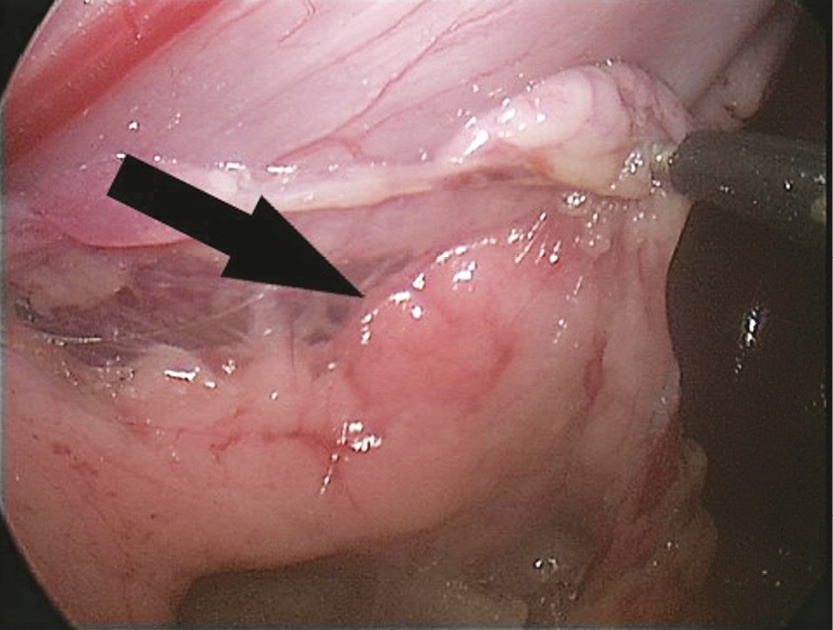

При осмотре поджелудочной железы визуализирован очаг плотной ткани в хвосте размерами 1 × 1,5 см (рис. 3).

Рис. 3. Очаг патологической ткани в хвосте поджелудочной железы

Fig. 3. Focus of pathological tissues in the tail of the pancreas